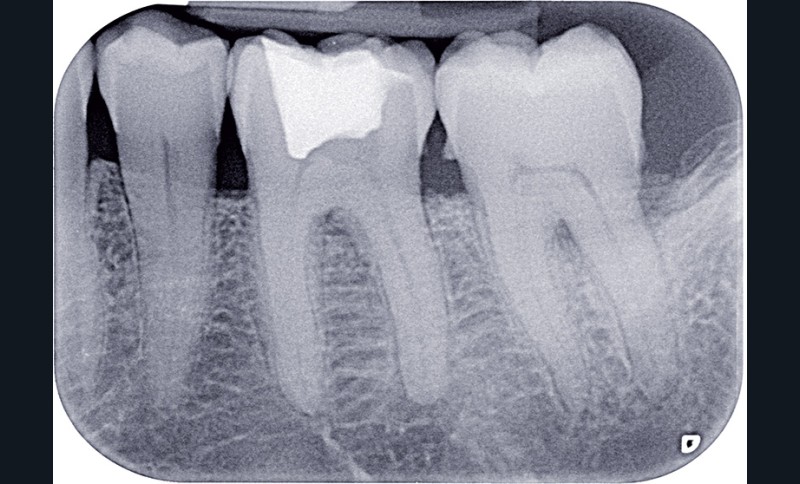

Dans ces situations, le praticien est conduit à dépulper et à restaurer les dents traitées endodontiquement. Les traitements doivent alors s’inscrire dans le concept du continuum endo-restaurateur qui a été défini comme étant « le processus spatio-temporel sans interruption ni rupture qui débute par l’accès à l’endodonte et s’achève avec la mise en place de la restauration prothétique d’usage » (1). Il existe bien une continuité, du traitement endodontique à la restauration fonctionnelle d’usage qui conditionne le pronostic et les résultats du traitement à long terme (fig. 2).